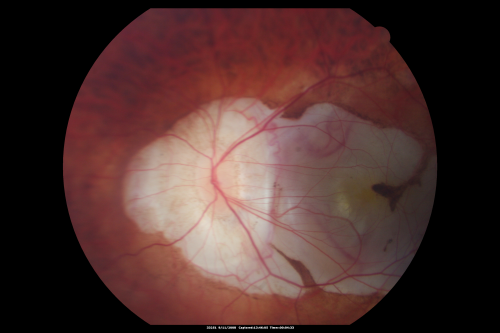

Posterior Staphyloma and Geographic Atrophy Myopic Degeneration

54-year-old man . He is a high myope. He has posterior staphylomas. He has had gradually changing vision for the last month or two. OD is 20/40, OS is 20/50.